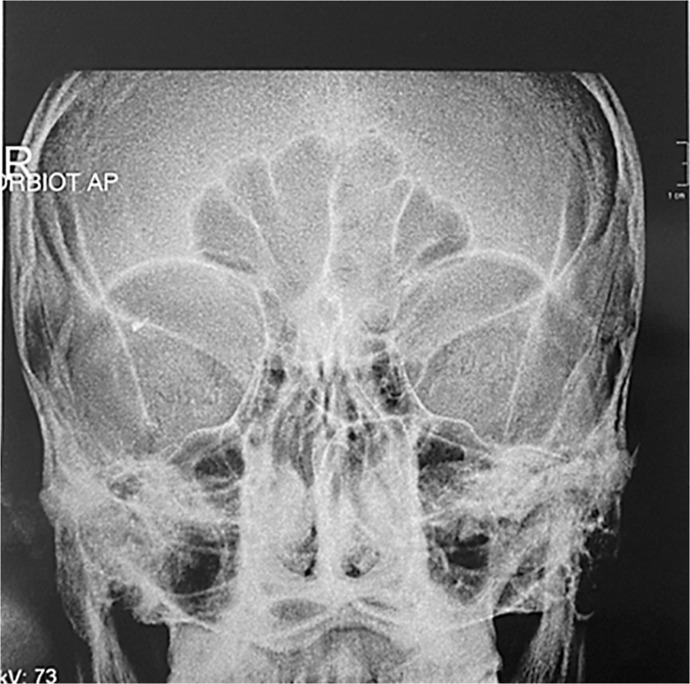

Case presentation: A 28-year-old male presented to the outpatient department after an alleged workplace accident. Initial assessment revealed significant diminution of vision, and on anterior segment examination with slit lamp, conjunctival congestion with no obvious entry point and no obvious scleral tear noted. Fundus examination by indirect ophthalmoscopy revealed vitreous hemorrhage, but the foreign body could not be localized due to extensive hazy media. Radiography of the orbit revealed an IOFB. The patient was managed surgically, and the intraretinal foreign body was removed using an intraocular magnet and intraocular forceps. The decision to remove the inert metal was considered because the patient had significant vision loss with vitreous hemorrhage.